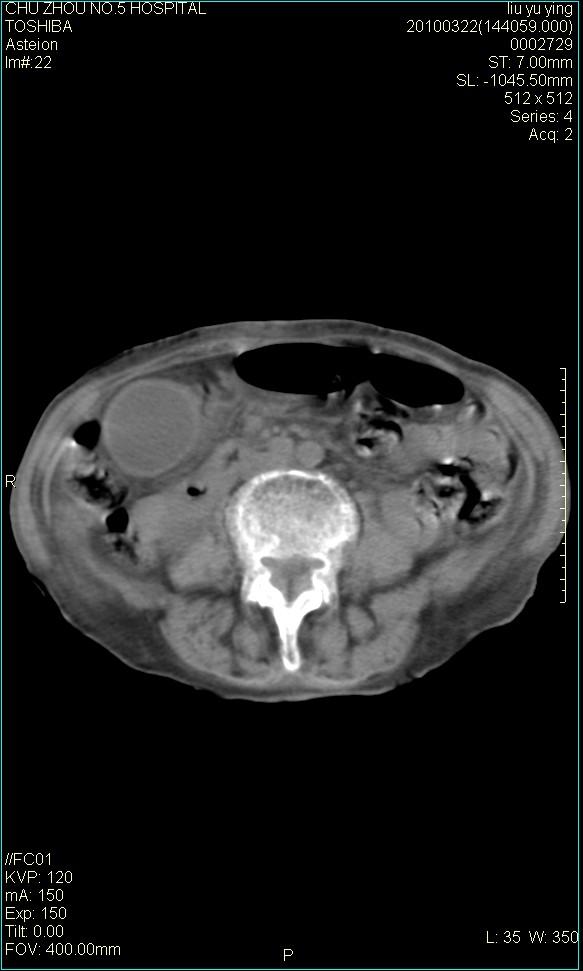

以下是引用科室第一人在2010-3-23 6:50:00的发言:[br]胆总管下段梗阻,多为肿瘤性病变,巨形胆囊,胆囊炎胆囊窝积液。[br]双侧胸腔积液,右降

以下是引用随光逐影在2010-3-23 8:12:00的发言:[br]1)胆系低位梗阻(肝内外胆管扩张,胆囊增大),原因待查。2)胆囊炎。3)双侧少量胸腔积液。4)降主动脉迂曲。